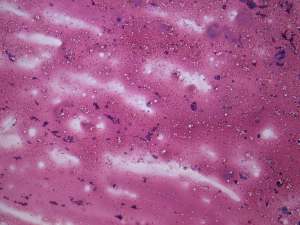

Surgery was performed because of cosmetic reasons. Histopathology disclosed benign hyperplastic nodular goiter.